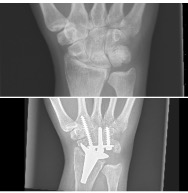

De ziekte bepaald wie ik ben, ondanks dat ik nooit wil toegeven dat ik veel minder kan. Ik heb ondertussen rechts een polsprothese en links is mijn pols half vastgezet. In augustus kreeg ik het verdict dat de botten in mijn handen en polsen weer verslechterd zijn en dat ik ooit de stap zal moeten nemen naar totaal vastgezette polsen.